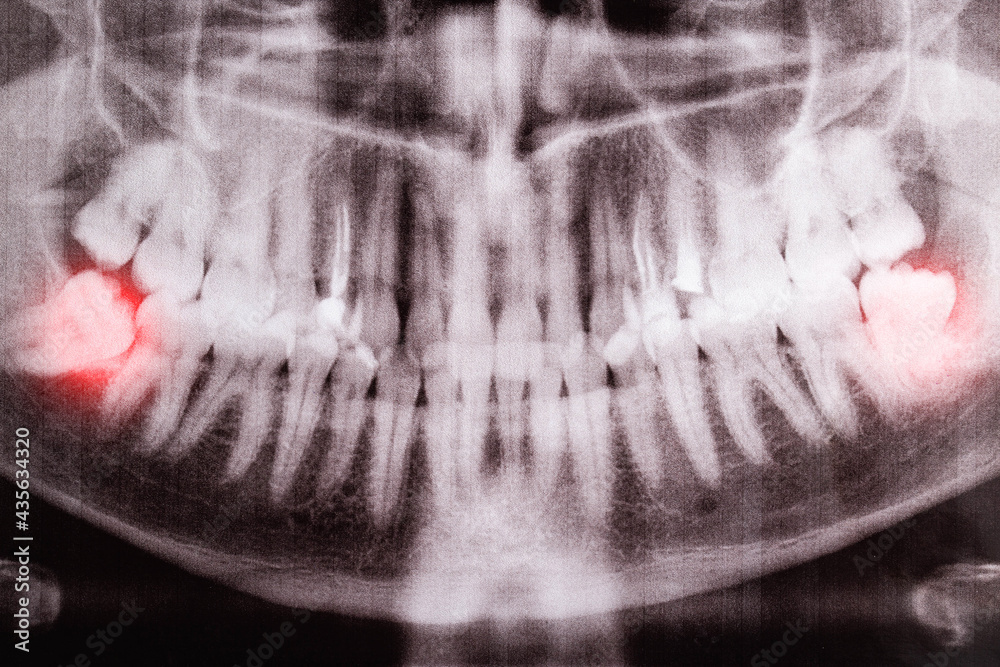

impacted wisdom tooth xray Impacted ray diagnosis

Impacted Wisdom Teeth X Ray Photos - TeethWalls

teethwalls.blogspot.comimpacted ray diagnosis

teethwalls.blogspot.comimpacted ray diagnosis